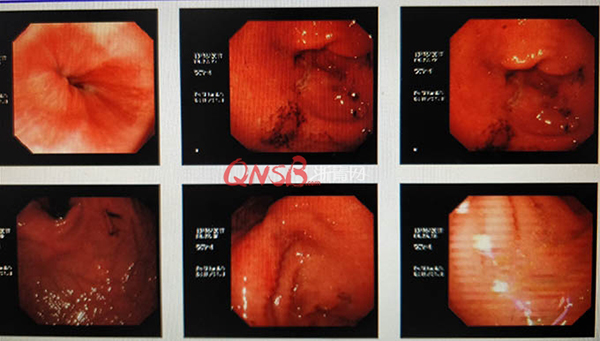

檢查結(jié)果出來后,小周大吃一驚,本以為自己的胃很健康,卻不想胃粘膜廣泛充血糜爛,長了兩個(gè)巨大的潰瘍(直徑大于2厘米),還有出血和咖啡色血痂。